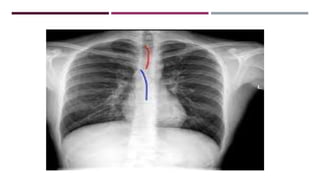

JUNCTION LINES

POSTERIOR JUNCTION LINE

ANTERIOR JUNCTION LINE

AZYGO-OESOPHAGEAL INTERFACE

PLEURO-OESOPHAGEAL STRIPE

PARASPINAL LINE